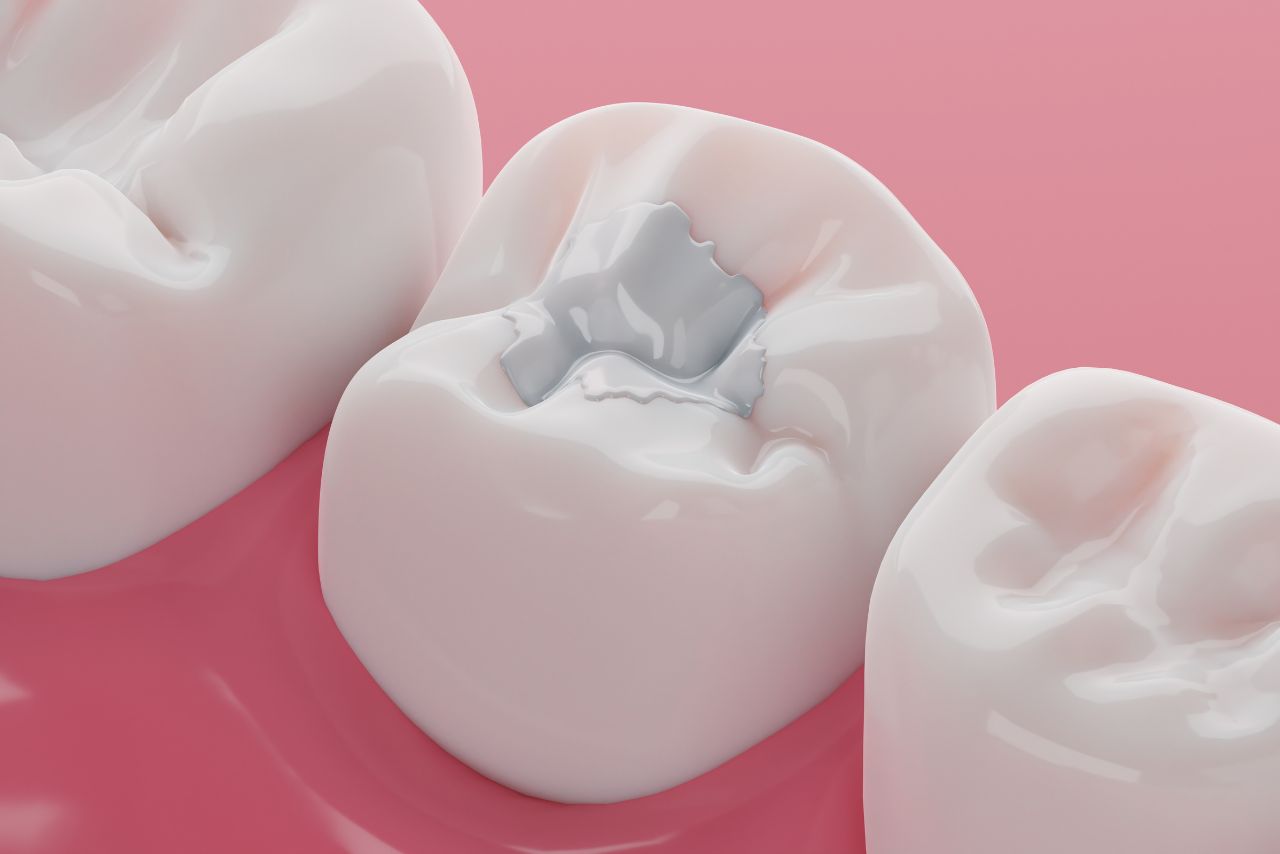

Le scellant est un traitement préventif, qui sert à protéger les sillons de l’émail. Informez-vous dès maintenant.